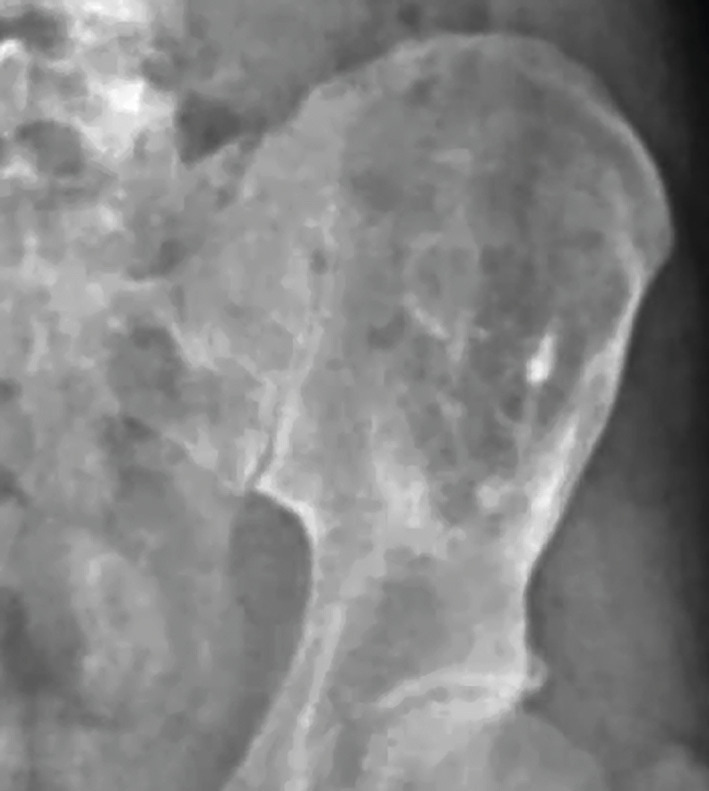

Arnaud, 37 ans, militaire sportif et asymptomatique, consulte avec les radiographies prescrites pour une expertise médicale initiale au parachutisme. L’aile iliaque gauche est le siège d’une lacune osseuse assez importante de découverte fortuite (fig. 1 ).